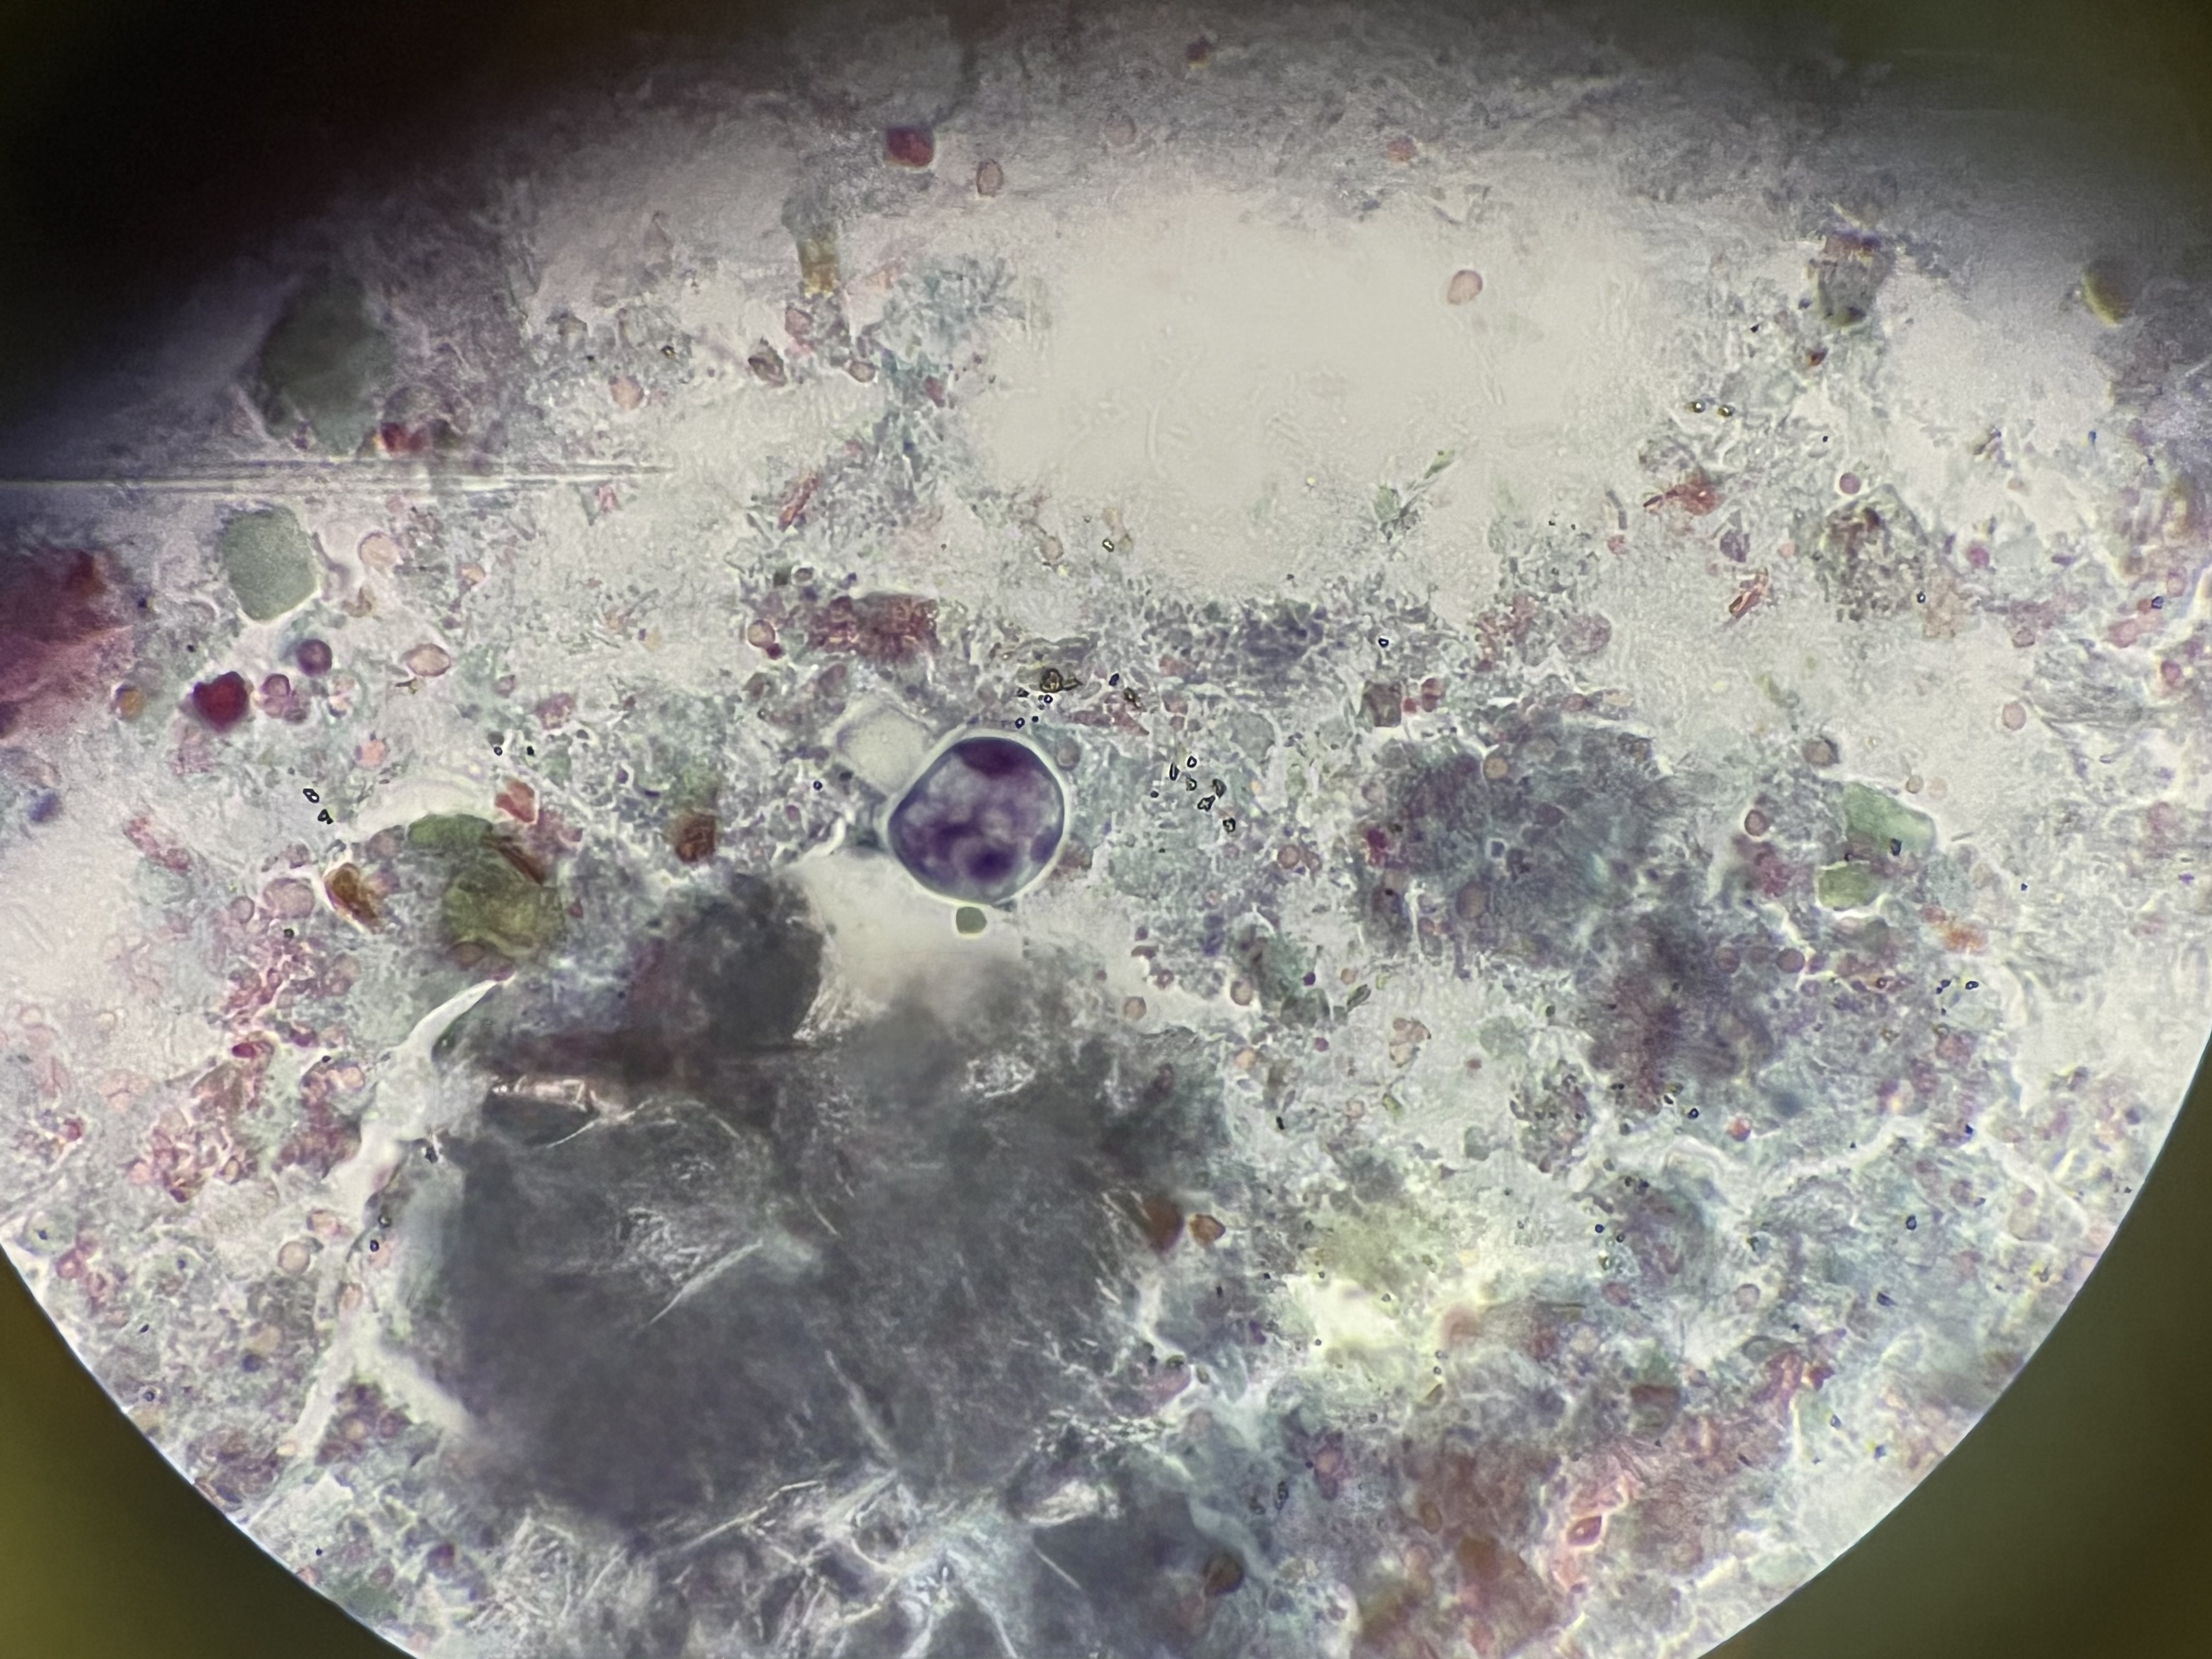

| Blastocystis hominis - faecal sample (the round thing in the middle) |

The photos above are all I took in December, apart from Graduation photos, which I can’t share. For anyone who wants to know more about the parasites show, you can find them on the CDC parasites A-Z website.